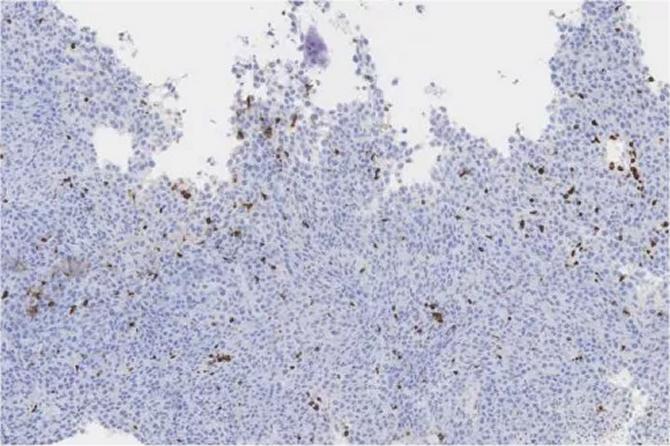

Tinción inmunohistoquímica de poblaciones de células T en el tejido tumoral colorrectal. (Foto: Piper Treuting/University of Washington)